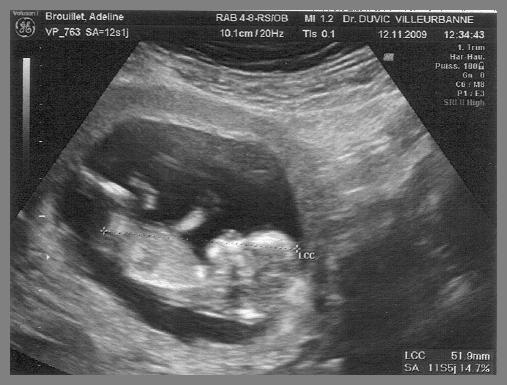

Coucou ! Me voici me voilà ! Nouveau petit locataire pour 9 mois dans le ventre de ma Maman ! J’y suis depuis environ 12 semaines et devrait pousser mon premier cri fin Mai 2010 ! Je mesure aujourd’hui environ 6cm de la tête au coccyx. Un petit hématome avait élu domicile avec moi lors des premières semaines, ce qui a expliqué que Maman ait été arrêtée 3 semaines mais ce n’est aujourd’hui plus qu’un mauvais souvenir. Ma grande soeur Louise veut une petite soeur donc pour elle c’est décidé ! Normal, Tchoupi, lui, il a une petite soeur ! Mais le destin choisira pour nous, et il choisira très bien !